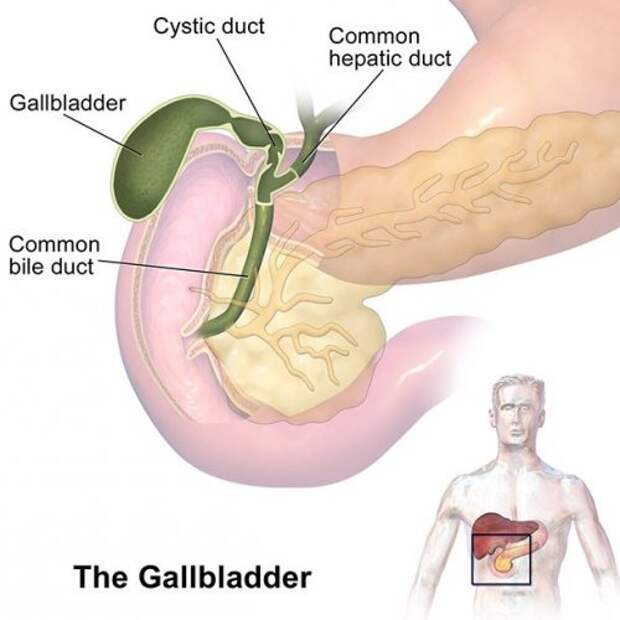

2. Желчный пузырь – это орган, в котором скапливается произведенная печенью желчь. Эта жидкость участвует во многих процессах, включая расщепление жиров.

Фото: BruceBlaus

2. Желчный пузырь – это орган, в котором скапливается произведенная печенью желчь. Эта жидкость участвует во многих процессах, включая расщепление жиров.

Фото: BruceBlaus